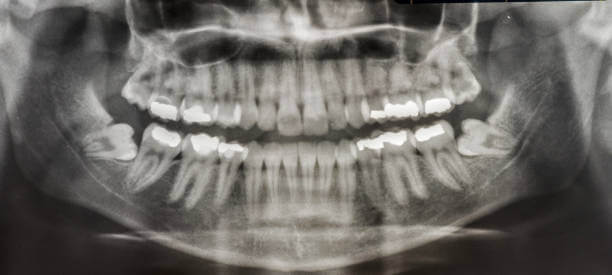

사랑니가 나는 이유는 명확하지 않지만 인류학자들은 사랑니가 진화의 신호라고 믿습니다. 과거에 인간은 날고기, 견과류, 뿌리와 같은 질기고 거친 음식을 먹었습니다. 그러다 1만 년 전 농사를 짓기 시작하면서 부드러운 음식을 먹기 시작했고 그 결과 튀어나온 턱이 점차 들어가기 시작했습니다.

인류의 턱이 작아지면서 입안 깊숙이 사랑니가 자랄 공간이 부족해졌고 이 때문에 사랑니는 눕거나 발치하는 등 썩거나 염증이 생기기 쉬운 모양으로 나오는 경우가 많습니다.

인간은 사랑니를 제외하고 상하 14개의 영구치를 가지고 있습니다. 중앙에 한 쌍의 앞니, 한 쌍의 옆 앞니, 한 쌍의 송곳니, 두 쌍의 작은 어금니, 두 쌍의 어금니가 있습니다. 이 두 어금니보다 작고 큰 어금니 바깥쪽으로 자라는 치아를 '사랑니'라고 합니다. 사랑니의 학명은 '제3대구치'로 세 번째로 큰 어금니를 의미합니다.

사랑니가 다 있게 되면 위턱과 아래턱 양쪽에 하나씩 총 4개가 됩니다. 약 7%의 사람들은 사랑니가 전혀 없으나 만약 가지고 있다면 치아의 수는 사람마다 1~4개로 다양합니다.

사랑니는 보통 정상적으로 나오고 깨끗하게 유지되면 문제없이 사용할 수 있습니다. 그러나 공간이 부족한 치열의 가장 안쪽 끝에 위치하는 경우가 많기 때문에 관리가 어려우며 각종 질환을 유발할 수 있습니다.

사랑니는 다른 치아에 비해 크기와 모양이 매우 다양합니다. 사랑니는 똑바로 나오지 않고 기울어져 있거나 누워있는 경우 잇몸에 묻혀 있는 부분이 많습니다.